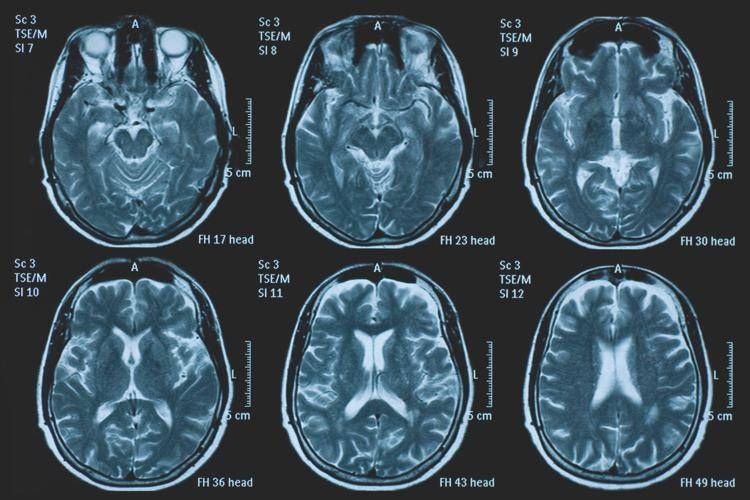

La Commissione europea (Ce) ha autorizzato la commercializzazione condizionata di tovorafenib come monoterapia per il trattamento dei pazienti di età pari o superiore a 6 mesi con glioma pediatrico di basso grado che presentano una fusione o un riarrangiamento del gene Braf o una mutazione Braf-V600, in progressione di malattia dopo una o più terapie sistemiche precedenti. Lo annuncia Ipsen, in una nota, precisando che si tratta della “prima terapia mirata” per questa patologia e che la decisione della Ce si riferisce ai 27 Stati membri della Ue, oltre a Islanda, Liechtenstein e Norvegia. Ogni anno in Ue vengono diagnosticati più di 800 nuovi casi di glioma pediatrico di basso grado (pLgg) con alterazione di Braf. Questo tumore cerebrale, nonostante sia classificato di basso grado (a lenta progressione), comporta un carico significativo e permanente che accompagna la persona per tutta la vita, causando spesso importanti compromissioni fisiche e neurologiche, tra cui perdita della vista, difficoltà di linguaggio e disfunzioni motorie, che possono incidere in modo significativo sull’istruzione, l’autonomia e la qualità di vita a lungo termine del bambino. Finora, molti bambini con pLgg hanno dovuto sottoporsi a interventi chirurgici invasivi, a più cicli di chemioterapia e a radioterapia, con conseguenti complicazioni della salute.